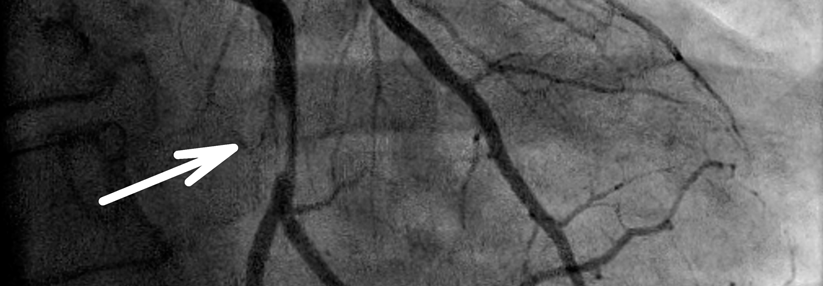

Atemluftanalyse: Gute Fitness halbiert das Risiko für Koronarereignisse

Eine geringe Fitness ist ein Alarmzeichen für drohende Herzprobleme – auch bei ansonsten guter Gesundheit. Auskunft über das konkrete Risiko gibt die…

Kardiologie